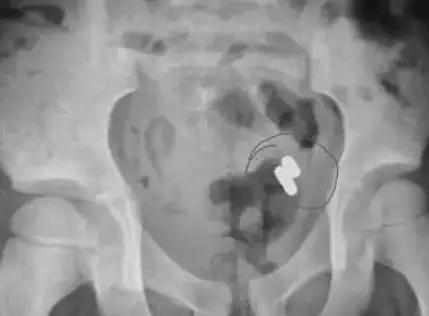

长春市儿童医院 消化内科 副主任 罗磊:通过结肠镜做这个手术。我们达到回盲部,也就是小肠和大肠交界处,发现了此异物,但并不是纽扣电池,是一个黑色的磁铁。

医生告诉记者,因为回盲部比较狭窄,正因为磁铁卡在了这个位置,所以未能顺着肠道排出。磁铁停留的这6天,由于异物摩擦,孩子的回盲部已经出现了充血、水肿和糜烂,如果磁铁再不及时取出,很有可能引起内脏损伤、肠道穿孔等并发症。

医生紧急为孩子进行了手术后,将磁铁取出。术后,经过观察,孩子恢复良好,已在18号办理了出院手续。